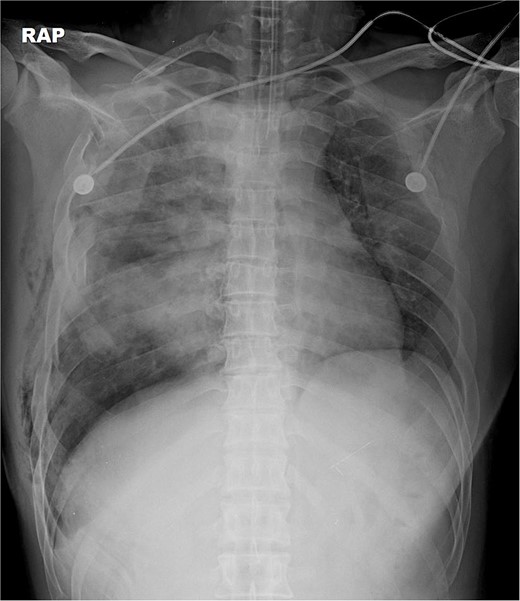

The thoracotomy incision was relatively small, ~8 cm in size, and the intercostal space was not spread to prevent further intraoperative chest wall damage. There were multiple lung lacerations in the upper, middle, and lower lobes with active bleeding. Bloody leakage continued through the avulsed parietal pleura and mediastinum. Hemostasis was achieved by suturing the deeply lacerated lung and packing with gauze (Combat Gauze ™ [Z-Medica QuikClot]) at the chest wall and mediastinum. The operation took 130 minutes. The transfusion of plasma, platelets, and red blood cells was balanced according to the following quantities: 10, 10, and 14 U, respectively. After surgery, the patient was transferred to the intensive care unit (ICU). The PaO2/FiO2 ratio was 52 mmHg with a Positive end expiratory pressure of 15 cm H2O, at a peak inspiration pressure of 30 cmH2O. ABGA showed pH 7.23, pCO2 42, and pO2 47. Veno-venous ECMO based on bilateral femoral vein cannulation was performed (Fig. 3a). Considering the patient’s hemorrhagic predisposition, heparin was not used. Disseminated intravascular coagulation (DIC) occurred along with acute renal failure. Antithrombin III infusion and continuous renal replacement therapy (CRRT) were initiated on the second hospital day. By the 5th day, oxygenation was achieved without ECMO support, followed by decannulation. On the 6th day, the second operation was performed in about 35 minutes. The gauze was removed, and no active bleeding or oozing was seen (Fig. 3b). The third operation, performed on the 13th day, was an open reduction of right ribs 3–7 for correction of flail chest and took 75 minutes (Fig. 3c). After open reduction, the flail chest improved, but the patient was not able to be weaned off the ventilator. Pneumonia and bacteremia developed. A tracheostomy was performed on the 15th day. CRRT was switched to hemodialysis, which was stopped on Day 28. The patient was discharged on the 47th day without tracheostomy. Ten months postoperatively, pulmonary function testing revealed forced expiratory volume in one second and diffusion capacity of carbon monoxide of 77% and 67% of predicted values, respectively. The chest CT and radiographs showed that the lungs had healed well, and there was no displacement of the ribs (Fig. 4). The patient recovered and returned to work.

Chest radiograph and CT scan 10 months after the accident. (a) Chest radiograph showed well-healed fractured ribs and expanded lungs without active lesions. (b)–(e) Non-enhanced axial chest CT images showed recovery from injury.